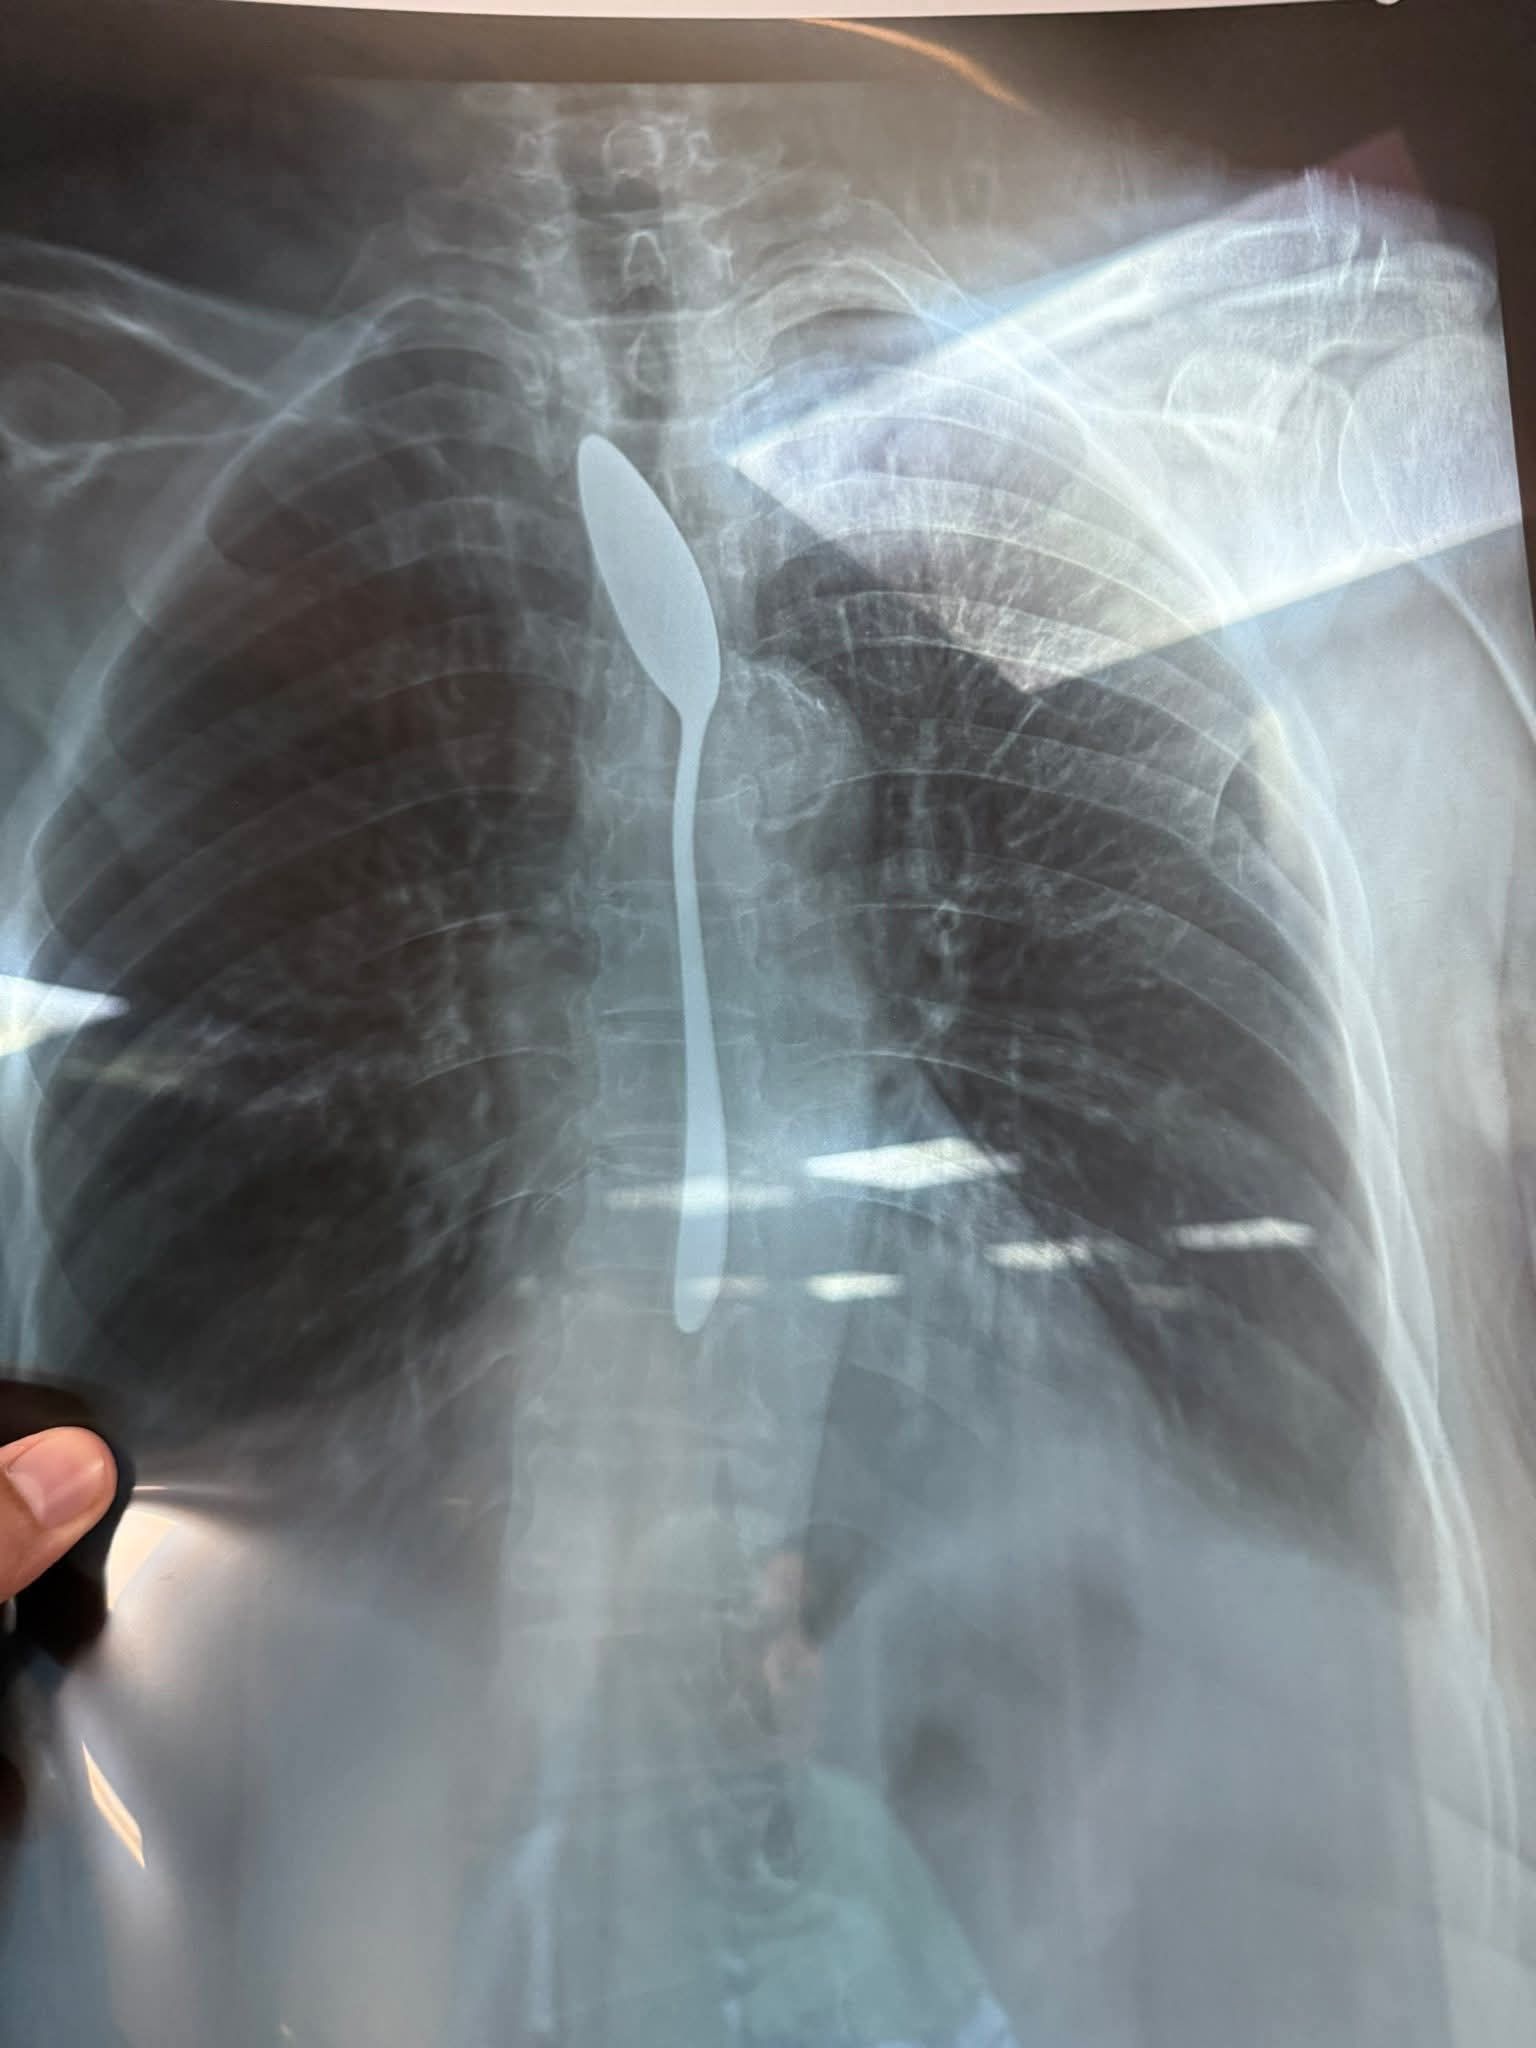

من جانبه، أكد الدكتور أحمد شهاب طبيب بقسم الجراحة العامة بمستشفى شبين الكوم التعليمى بمحافظة المنوفية، على وصول حالة مسنة لطوارئ مستشفى شبين الكوم التعليمي تبلغ من العمر 70 سنة ترافقها نجلتها تؤكد معاناة والدتها بسبب قيامها ببلع ملعقة صغيرة .

على الفور تم إجراء إشاعه للسيدة وتبين وجود ملعقة، على الفور تم تجهيز السيدة وتم إجراء الجراحة لها داخل غرفة العمليات في وقت قياسي من 5 لـ 7 دقايق، وتم استخراج الملعقة.

الاشاعة